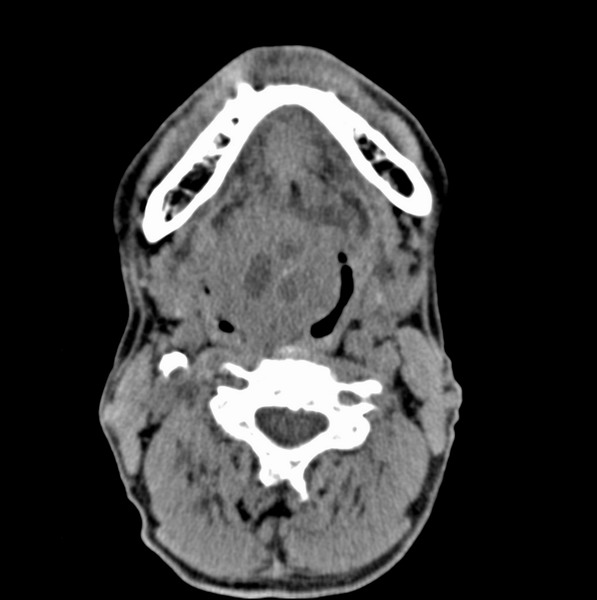

男、60、舌根肿物。

舌垂直肌和横肌影处肿块影,边缘不规则,咽腭扁桃体及舌下间隙脂肪影消失,病变侵及口咽。

考虑-----舌根癌

舌跟软组织肿块,较大有坏死,钙化。结合年龄一般是恶性肿瘤。

舌根部较大软组织肿块,其内见坏死低密度区及钙化影;考虑舌根癌可能。